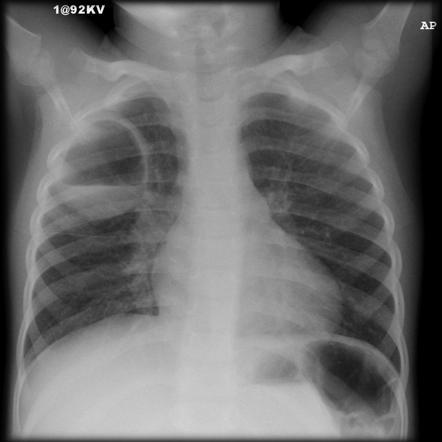

Rx: broncopneumonia ou lobar

Rx: infiltrado intersticial